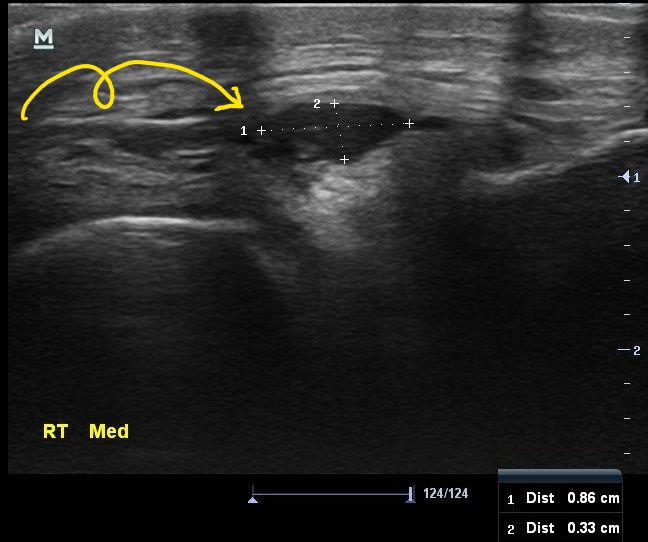

이 환자분의 진짜 문제는 초음파 검사에서 발견되었습니다.

나 : 연골주사 맞아도 아픈 이유가 있었네요

나 : 내측반월판 연골 부위에 물혹이 하나 생겨있습니다.

나 : 네 결절종이라고 하는 건데요... 무릎을 굽히실때 이게 주변 조직을 누르면서 통증이 발생한듯 합니다.

나 : 초음파 보면서 주사기로 물혹속 내용물을 제거해봐야 할거 같습니다.